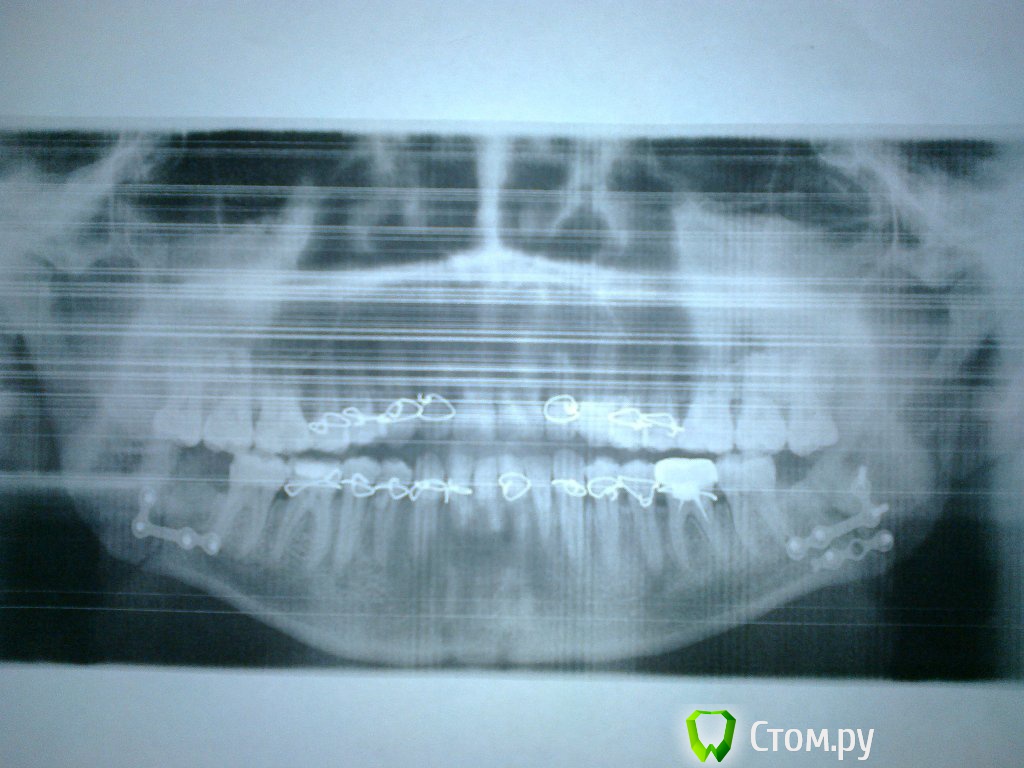

Sahan Опубликовано 9 июля, 2014 Поделиться Опубликовано 9 июля, 2014 (изменено) Вот посмотрите снимки за 11.06. и за 23.06. Где за 23 немного дернулся при снимке, вот как по середине и съехала челюсть. Скажите, что по снимкам, все правильно сопоставлено и срастается?Это не брак снимка а смещение отломков. У вас тройной перелом. В области углов и в области 3.3 зуба. Переломы в области клыков плохо срастаются. Поэтому когда вам сняли тяги в этой области отломки разьехались и зубы перестали смыкаться в прикусе. Я бы удалил зуб из линии перелома и дал бы походить с тягами 2 недели. Изменено 9 июля, 2014 пользователем Sahan Ссылка на комментарий

Bier Опубликовано 9 июля, 2014 Поделиться Опубликовано 9 июля, 2014 Саша, а где там линия перелома? 1 Ссылка на комментарий

АнтонТЛТ Опубликовано 9 июля, 2014 Поделиться Опубликовано 9 июля, 2014 Саша, а где там линия перелома?+1Тогда по этому снимку еще и верхняя челюсть сломана? 1 Ссылка на комментарий

Sahan Опубликовано 9 июля, 2014 Поделиться Опубликовано 9 июля, 2014 Саша, а где там линия перелома? http://i1172.photobucket.com/albums/r579/Shnsahan/th_a22ee03e14af60ac654f4eb4127c6ec1_zpsa7caef42.jpg Ссылка на комментарий

ivanich 82 Опубликовано 9 июля, 2014 Автор Поделиться Опубликовано 9 июля, 2014 Александр, а на этом снимке третий перелом у меня чудесным образом сросся за неделю? Ссылка на комментарий